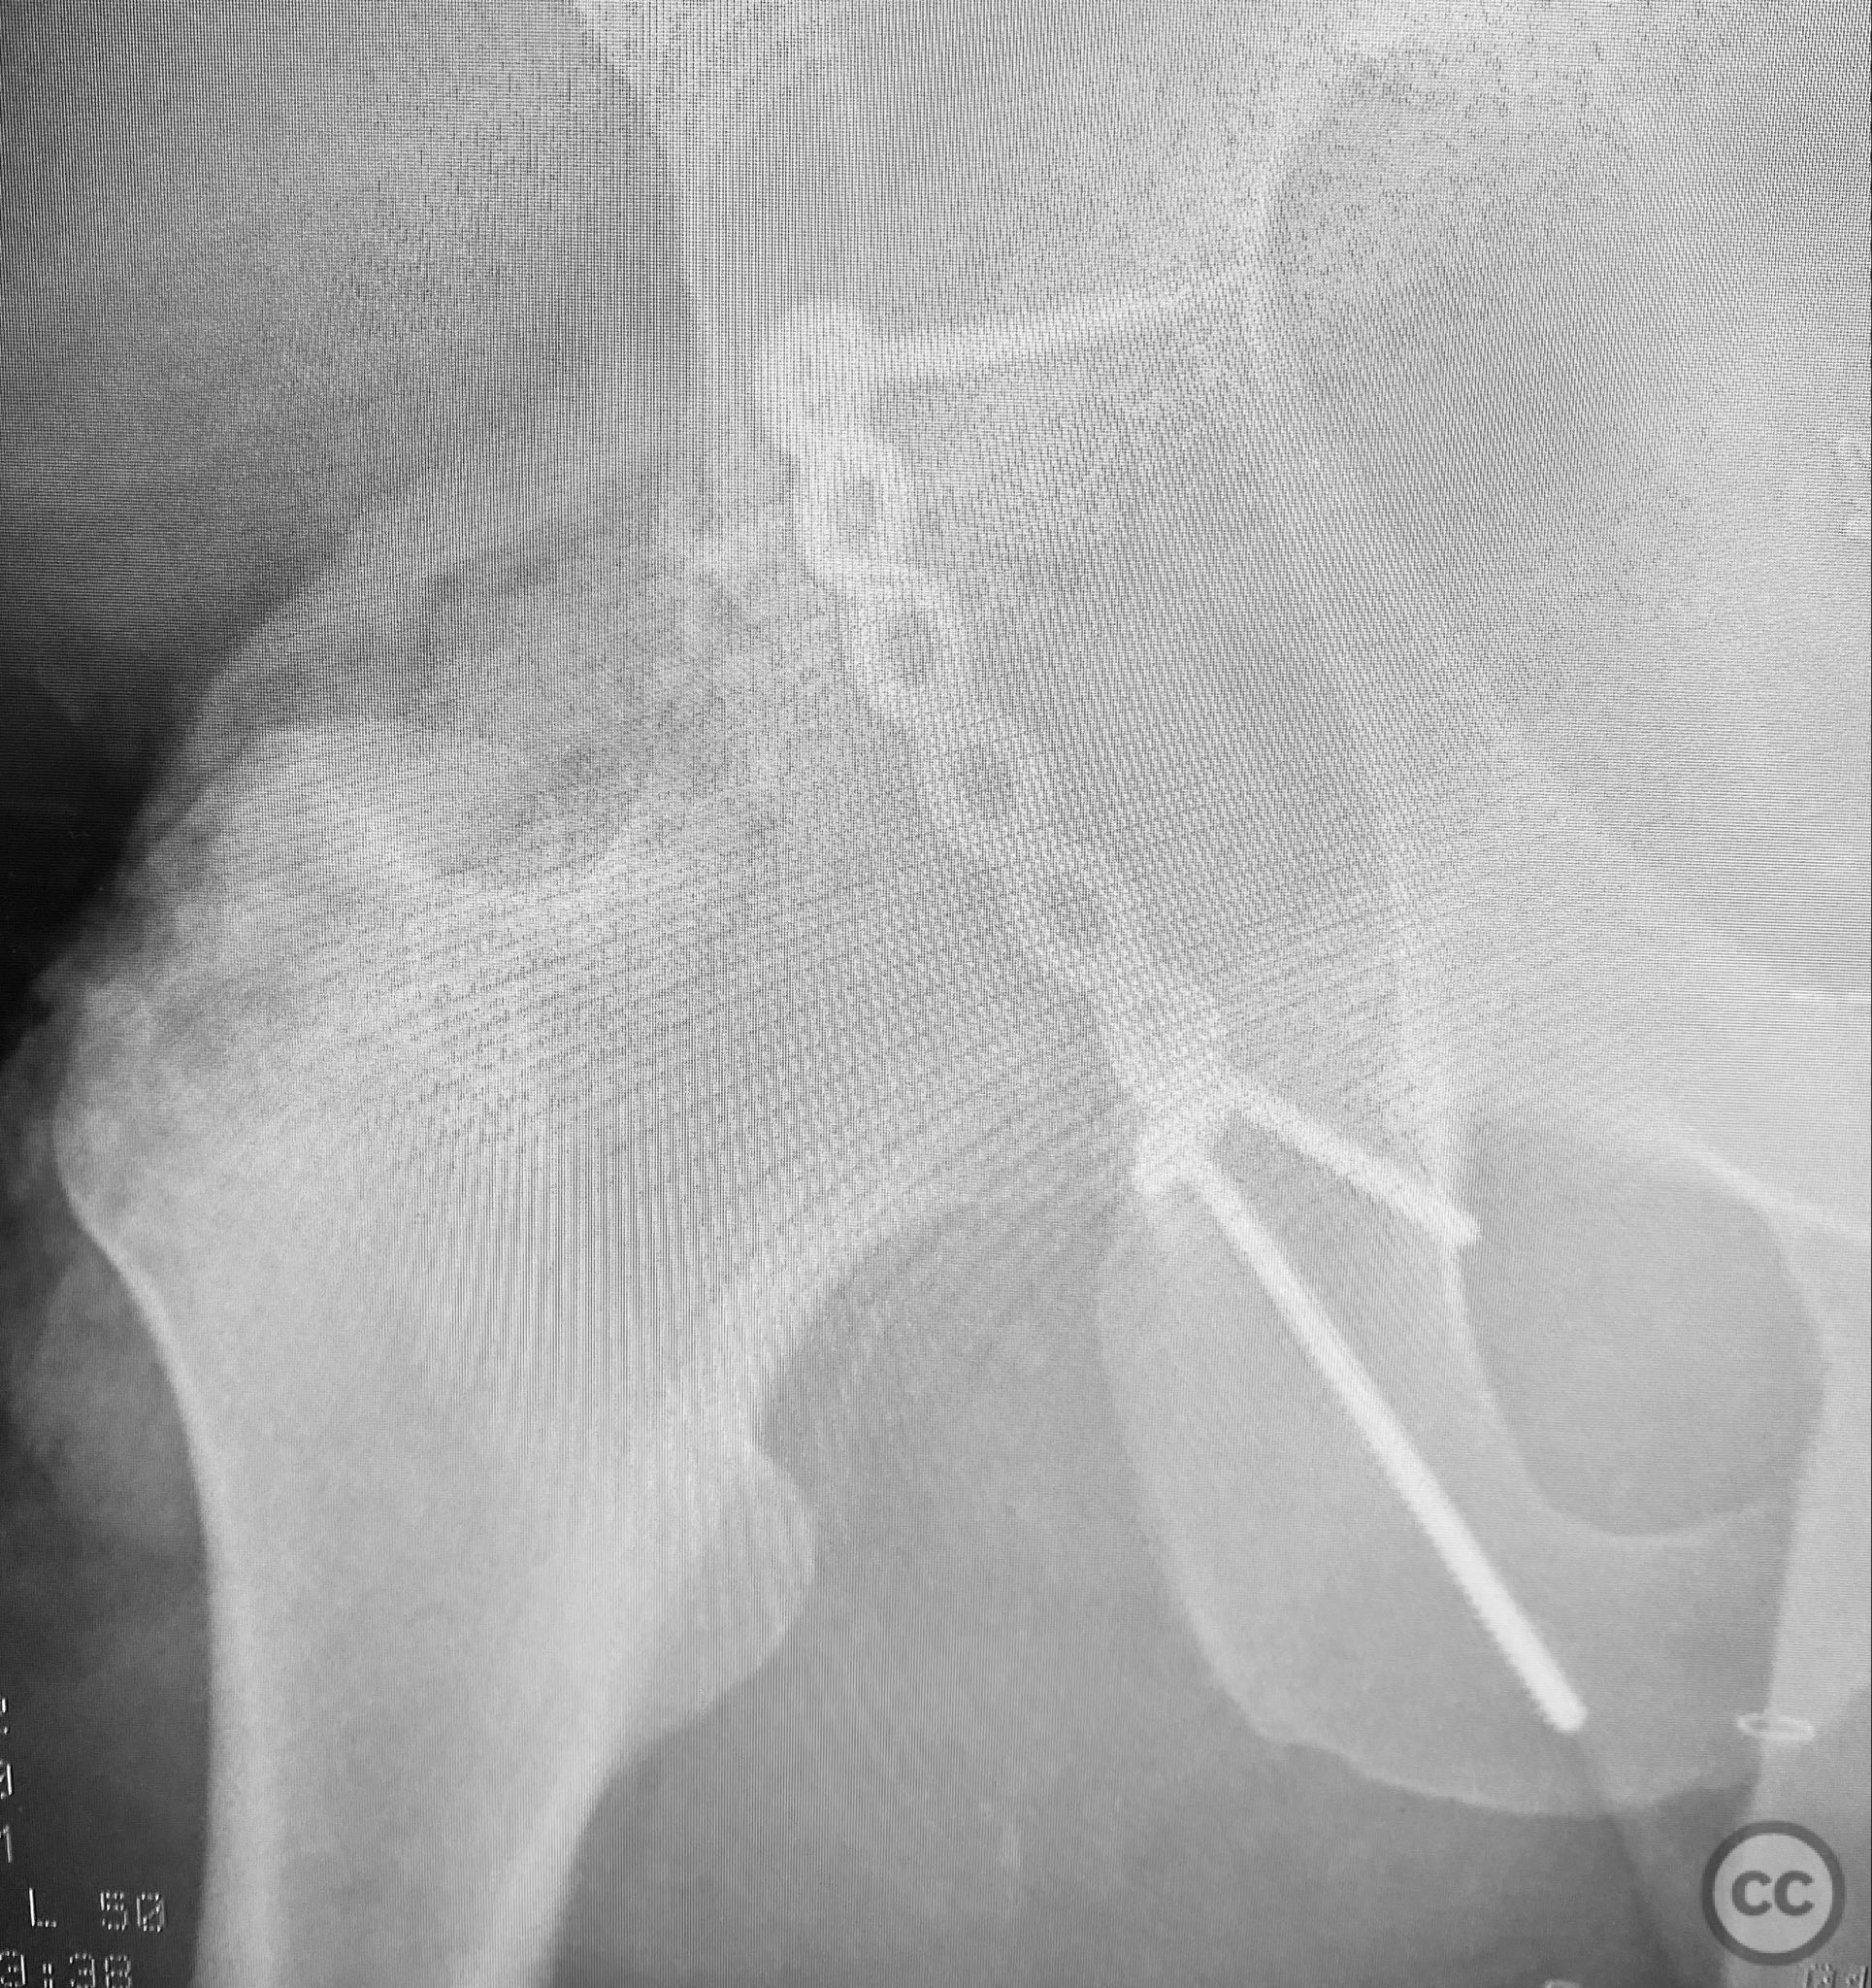

Clinical and radiological findings:  A patient presented with a seemingly non-comminuted, wide, and long posterior wall (PW) acetabular fracture fragment. Axial computed tomography (CT) images demonstrated the thickness of the PW fragment, the articular surface, and multiple areas of subchondral impaction. Preoperative planning identified the size, location, and depth of the impaction zones, as well as an essentially nondisplaced transverse acetabular fracture line, which was not readily apparent on initial imaging. No significant displacement of the transverse component was noted. The AO/OTA classification is 62-B1.3 (posterior wall and transverse acetabular fracture).

Planning remarks:  The preoperative technical plan included a prone Kocher-Langenbeck (KL) approach to access the posterior column and wall. The plan entailed elevation and reduction of impacted articular fragments, bone grafting of subchondral defects, anatomical reduction and provisional fixation of the posterior wall fragment, and definitive fixation with a contoured plate. Intraoperative fluoroscopy was planned to guide additional screw placement through the plate to stabilize both the posterior wall and the transverse fracture line. A supplementary medial plate was planned to augment fixation of both the posterior wall and transverse components.

Intraoperatively, elevation and reduction of impacted articular fragments were performed, followed by bone grafting of subchondral defects. The posterior wall fragment was anatomically reduced and initially stabilized with a contoured plate. Intraoperative fluoroscopy (obturator oblique view) was utilized to guide placement of an additional screw through the plate above the joint, traversing both the posterior wall fragment and stabilizing the transverse fracture line. A supplementary medial plate was applied to further support both fracture components. Postoperative CT imaging confirmed satisfactory reduction of both the posterior wall and transverse fractures, as well as restoration of articular congruity in previously impacted areas. Consideration is given to whether initial reduction and lag screw fixation of the transverse component prior to plate application may have improved reduction; however, final imaging demonstrated acceptable alignment.